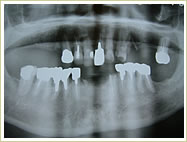

症例 54歳 男性 インプラント埋入数:11本 画像拡大

治療前 治療後